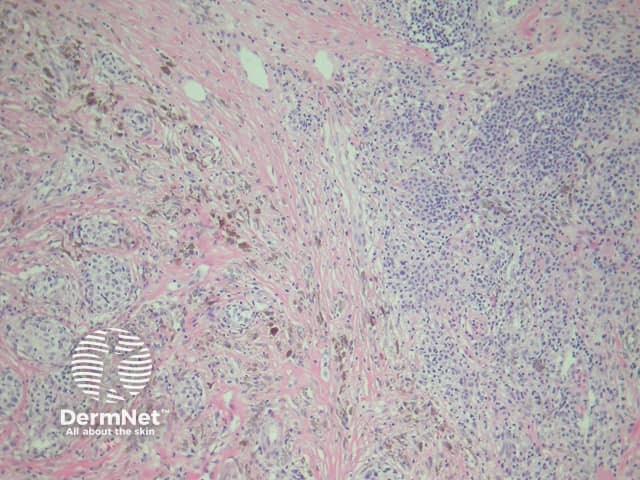

Cellular blue naevus is generally much larger than a common blue naevus and usually involves the entire dermis. The superficial subcutis is also often involved. The architecture is a rather distinctive mass composed of a lobular tongue or tongues into deep dermis (figure 6). The cellular density is markedly higher when compared with regular blue naevi. The cells may be round, oval or fusiform. Multinucleate giant cells are occasionally noted in the cellular areas and may be numerous in some cases.

Necrosis and/or numerous mitoses suggest that the tumour is an unusual melanoma rather than a cellular blue naevus.

Figure 6